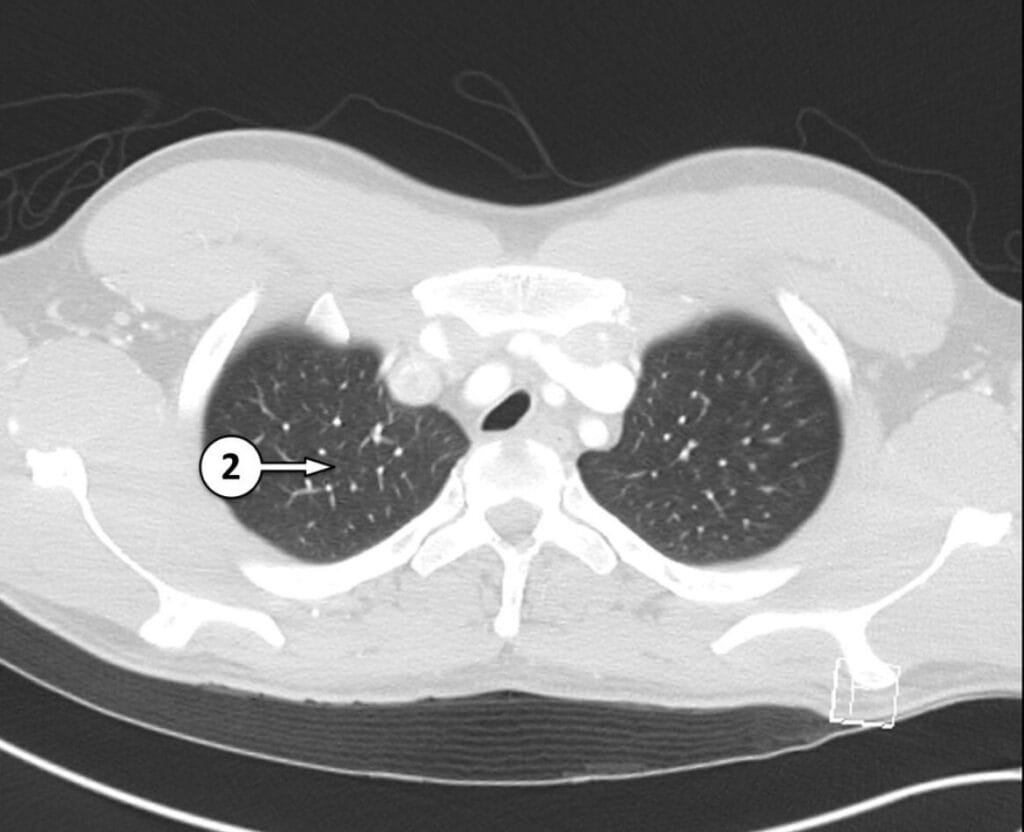

2. apical segment of RUL